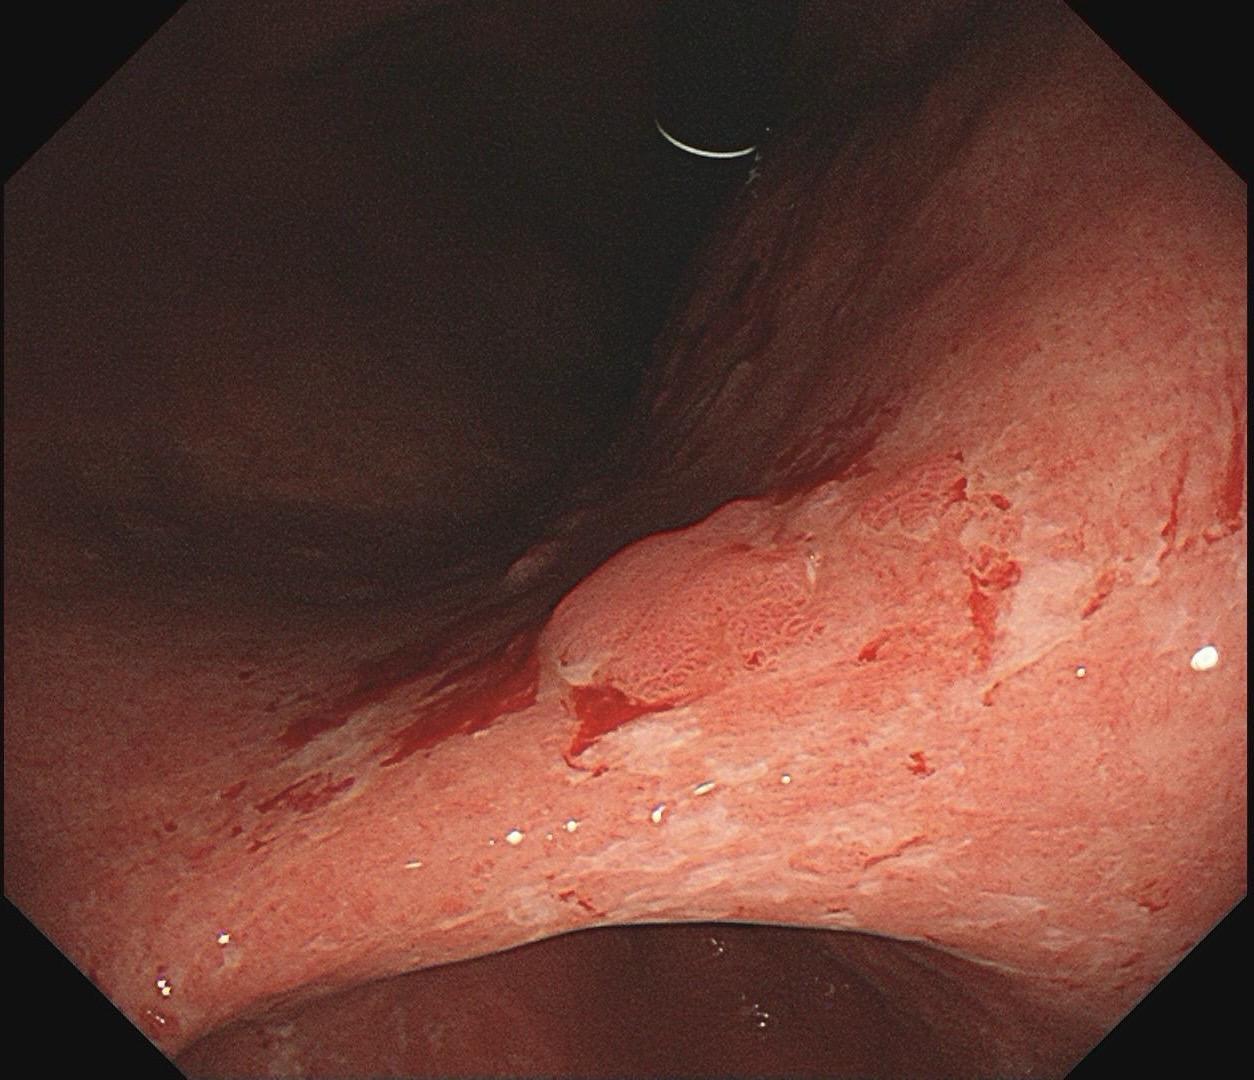

男,61岁,胃巨大褪色调病变。答案在最后一张图片,你猜对了吗? 患者因上腹部饱胀行胃镜检查,Hp阴性背景,胃窦至贲门下见一巨大褪色调病变,边界清晰,病变相对表浅,未见明显溃疡及隆起,胃壁较柔软,充气顺应性佳,予多点活检确诊,拟外科手术行全胃切除。做这么多年胃镜,还是第一次遇到这样的……